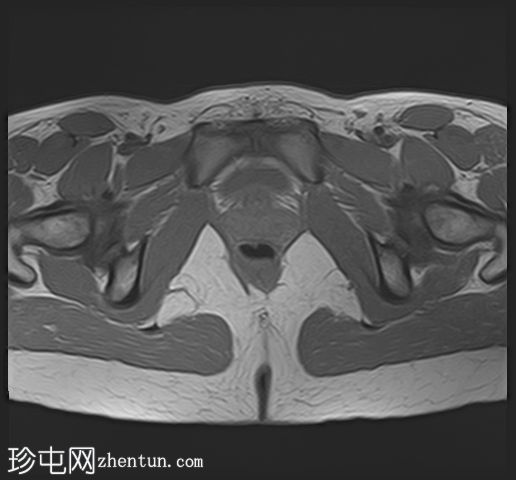

轴位

T2加权像

在右侧附件区可见一较大病灶,最大轴位和头尾径约为3 x 3.8 x 3.7 cm。该病灶在T1加权像上呈高信号,脂肪抑制像上无信号抑制,在T2加权像上呈低信号(阴影效应)。病灶壁可见T2暗点征结节,增强扫描后未见明显强化。

右侧附件区可见两个较小的类似病灶,最大径约1.2 cm。

双侧卵巢呈多囊性形态,优势卵泡保留。符合多囊卵巢(PCO)的影像学表现,T2加权像呈高信号,T1加权像呈低信号,并可见薄壁强化。

右侧道格拉斯窝内可见少量游离液体,可能为反应性积液。